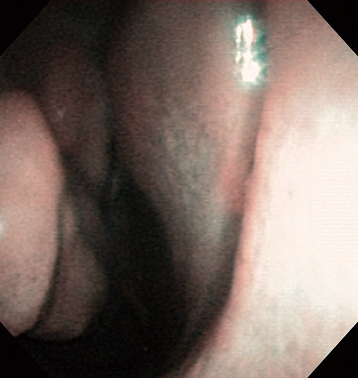

Right Epistaxis (Hypertensive Epistaxis) Aged 81, male

white light

NBI

Comment:

Hypertensive epistaxis on the 2nd day after onset. The suspected bleeding region was identified on nasal septum with NBI before epinephrine spraying. However, 5 minutes after epinephrine spraying, it was possible to identify the bleeding region more clearly.

Images and comments by Dr. S. Takano <ENF-V2>